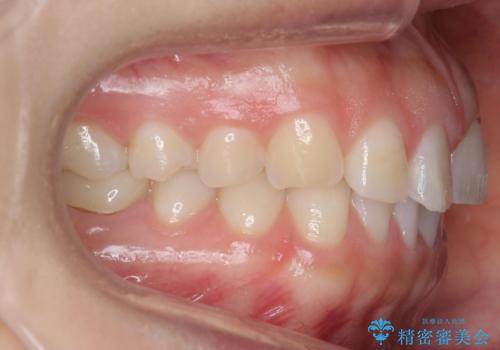

- 下の前歯のがたつきを治したいとのことでした。

上の前歯のちょっとしたねじれも治療しています。

軽度だったため、部分矯正のコースで短期間で治療しました。

下の歯並びを並べるため、わずかに歯を削合しています。

そうしないと、前に出て上の前歯に強く当たってしまうためです。また、後戻りを防ぐ効果もあります。

年齢を重ねてくると、下の前歯が目立つようになるので治療しておくと若々しい印象を保つことができます。